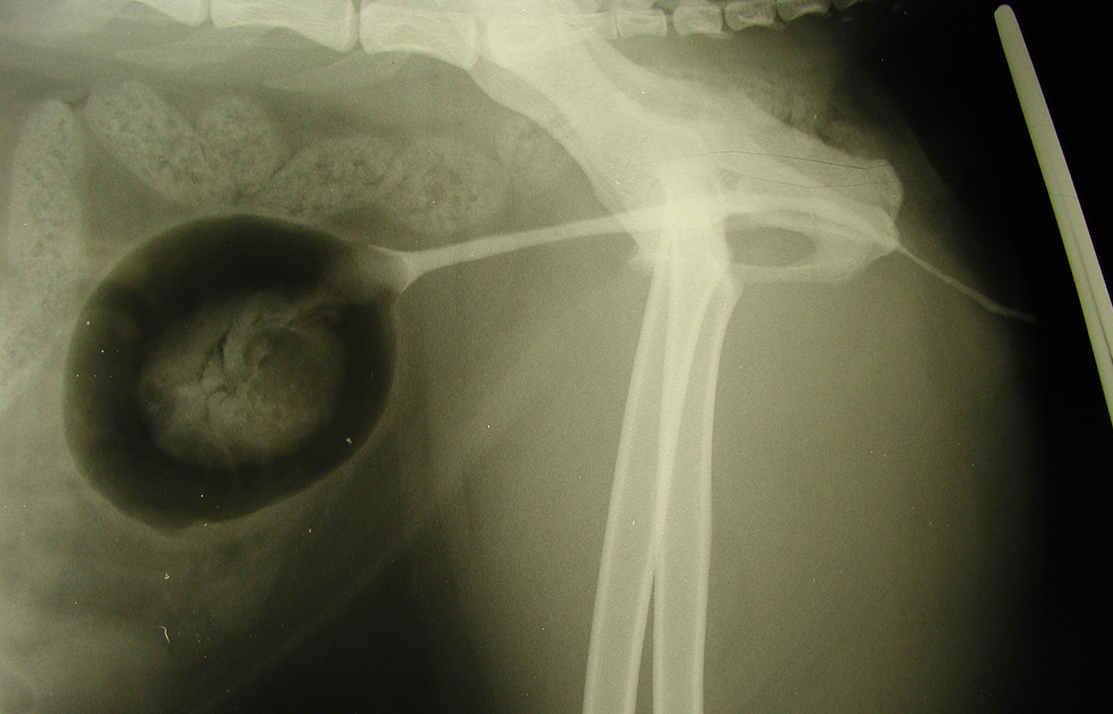

What is being shown in this radiograph and what are the possible causes?

Enlarged kidney —> increased soft tissue opacity in kidney

DDX = Cysts, haemorrage, abscess, neoplasia, granulomatous inflam, hydronephrosis

Metastasis of neoplasia (smaller circles)